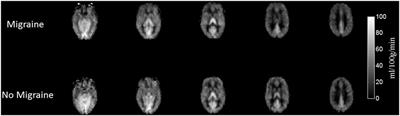

Published on 28 Jun 2017

in Headache and Neurogenic Pain